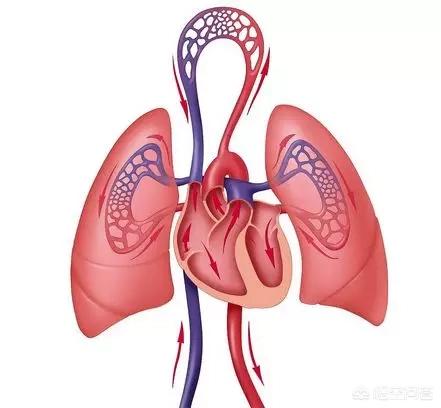

第5に、心臓病や肺気腫など、より深刻な病気を患っている人々である。酸素をより多く必要とする傾向があり、酸素が不足しないように呼吸をたくさんするため、口が渇きやすい!

III型:心肺障害

心肺機能が低下している人、心臓病や肺気腫の人は、より多くの酸素を必要とする傾向があり、酸素が不足しないように激しい呼吸をする!

早起きした後、バルコニーに行ったり、窓を開けたり、新鮮な空気の場所を探して深呼吸をすると、古いものを吐き出して心肺機能を整えることができる。

吸うときは腹部をやや外側に開き、吐くときは腹部を内側に閉じ、呼吸を司る横隔膜が沈むようにすることで、胸腔の容量を大きくし、肺の機能を拡大させ、新旧の呼気の目的を達成し、心臓と肺の機能を調整する。